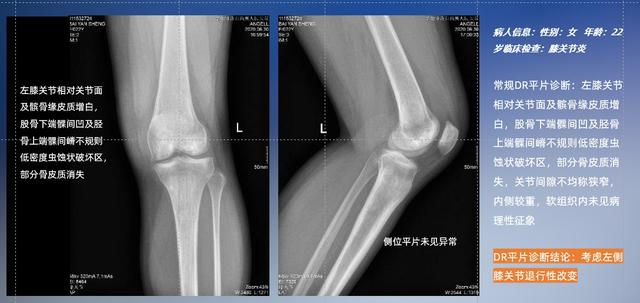

以膝关节疾病检查为例,膝关节在解剖学意义上是一种较为复杂的最大关节,由胫骨上端、股骨下端及髌骨组成。在股骨与胫骨的关节面之间存在两块半月板,分别处于内侧、外侧。膝关节的运动主要为伸、屈,在半屈位时可进行小幅度的旋外、旋内运动。随着现代人们体育生活以及肥胖的增加,膝关节疾病出现高发趋势,特别是关节磨损、膝关节炎与骨关节炎等关节退行性改变,长时间的内翻负荷会造成内侧关节软骨、骨性关节面的磨损。目前针对此类疾病的检查主要为平片下的负重位检查、CT检查以及MRI检查,相较于非负重位检查,负重位检查能更加真实反映膝关节结构中胫骨、股骨、髌骨实际对位关系和关节面的形态特征及关节间隙大小,对膝关节骨关节病诊断准确率高。

普通平片扫描与WR-3D扫描前后诊断结果对比

与此同时,数字化X线摄影技术相较于CTMRI来说,能快速获取真实、直观、满足临床需要的影像。DR的图像具有图像层次丰富、空间分辨力高、影像边缘锐利清晰、密度分辨力高级细微结构表现出色等特点,针对膝关节解剖结构数字化X线摄影技术应用价值很高,尤其是是对骨小梁与骨皮质的显示非常清楚。在负重位状态下,数字化X线三维摄影扫描与重建,能够更好的呈现受检者关节受力改变的状态。388vip太阳集团科技创新的WR-3D动态三维数字化X线摄影技术,通过数字化X线摄影完成三维扫描并重建三维影像信息,包括MPR多平面重建、MIP重建以及VR绘制。扫描时间短,剂量相较于CT设备大幅缩减,同时成本更低,在临床诊断以及医疗方案制定中具有极大的价值意义。相较于普通平片下的负重位扫描,负重位动态三维扫描摄影技术能够避免二维状态下的组织结构重叠、密度分辨率不足、组织解剖结构难以分辨等问题,WR-3D支持多角度的动态三维摄影观察,能全面的呈现被检查部位在多个角度下三维影像信息,极大的减少了二维负重位检查的漏诊率。